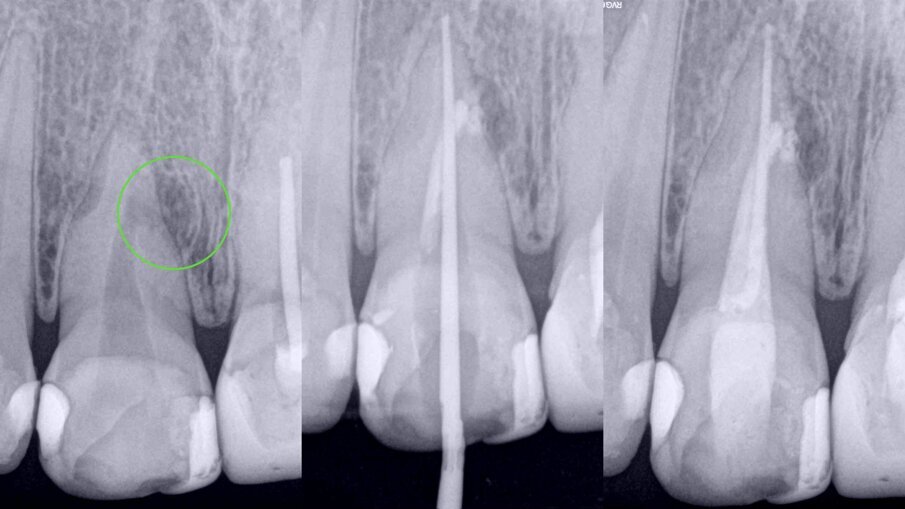

Figs. 6a–c: Radiographic sequence of the treatment performed in tooth #11. Initial radiograph. The root resorption and lateral radiolucent area were evident (a). Working length measurement at the level of the resorption (b). Root resorption repair with a calcium silicate-based material (c).

Figs. 7a–c: Radiographic sequence of the treatment performed in tooth #11. Initial radiograph. The root resorption and lateral radiolucent area were evident (a). Master cone fitting at the level of the complete working length (b). Completed root canal therapy (c).

Fig. 8: Radiographic sequence of the treatment performed in tooth #11. Initial radiograph. The root resorption and lateral radiolucent area were evident (a). Completed root canal therapy (b). Three-year follow-up radiograph showing complete healing of the lateral radicular radiolucent area and the correct sealing of the resorption (c).

During the first appointment for root canal therapy, it was not possible to reach the complete length of the root canal, because the files tended to go inside of the mesial resorption. It was decided to seal the resorptive defect (Fig. 6a–c) using CeraSeal sonically activated using the EQ-S device (Meta Biomed; see video below).

At the second appointment, the material placed at the resorption was completely hard. That hard barrier allowed the file to pass through the entire length of the physiological root canal. The root canal therapy was finished using CeraSeal as the endodontic sealer (Fig. 7a–c). The three-year follow-up radiograph showed complete healing of the lateral radicular radiolucent area (Fig. 8a–c).